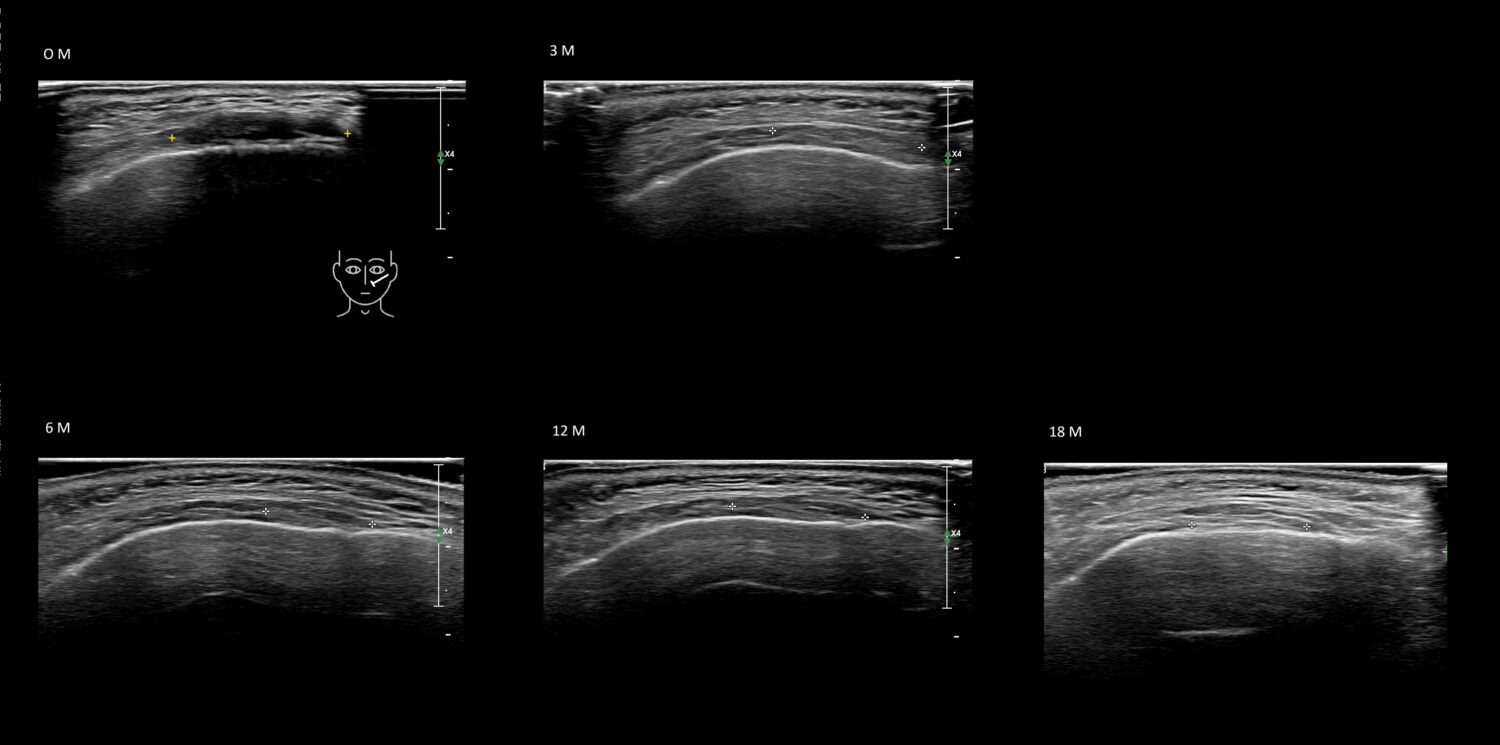

Fillers

Draw in the image on the right where the fillers are located. To check if your answer is correct, please click on the secondary image.